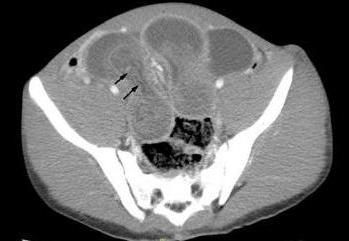

A CT scan of the abdominopelvic region was obtained to rule out bowel obstruction. An axial CT image showed significant distention of the distal ileal loops with concentric alternating rings of high and low attenuation and swirling of the mesenteric fat and mesenteric vessels (Figure 1, above). Figure 2 (left) shows the intussusceptum (arrows), with an accompanying complex of mesenteric fat and blood vessels, surrounded by the thick-walled intussuscipiens. Surgery was performed to prevent vascular compromise and bowel necrosis. Operative findings revealed ileal intussusception and intestinal necrosis secondary to an invaginated Meckel’s diverticulum. Postopertaively, the patient did well without any complications.

CT usually reveals a bowel-within-bowel configuration, with mesenteric fat and mesenteric vessels- a clinical picture pathognomonic for intussusception (Figure 2). CT imaging is useful in the diagnosis of intestinal obstruction, but it is not helpful in determining the cause of intussusception, because the lead point is often small and hidden within the intussusceptum.5